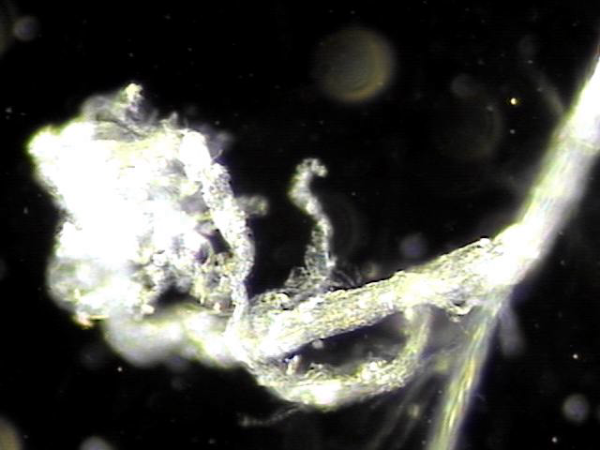

전립선과 사정관 그리고 사정관입구의 결석 치료중 사정관의 좁은 입구와 전립선관의 막혀 있는 입구로 커다란 결석이 배출시 압력으로 좁아져 있거나

막혀 있던 섬유화된 입구의 손상이 예상되는 현미경학적 사진입니다.

This is a microscopic image taken during the treatment of stones in the prostate, ejaculatory ducts, and the ejaculatory duct orifices.

It shows that large stones being expelled through the narrowed or obstructed fibrotic openings of the ejaculatory and prostatic ducts likely caused mechanical damage due to pressure during expulsion.